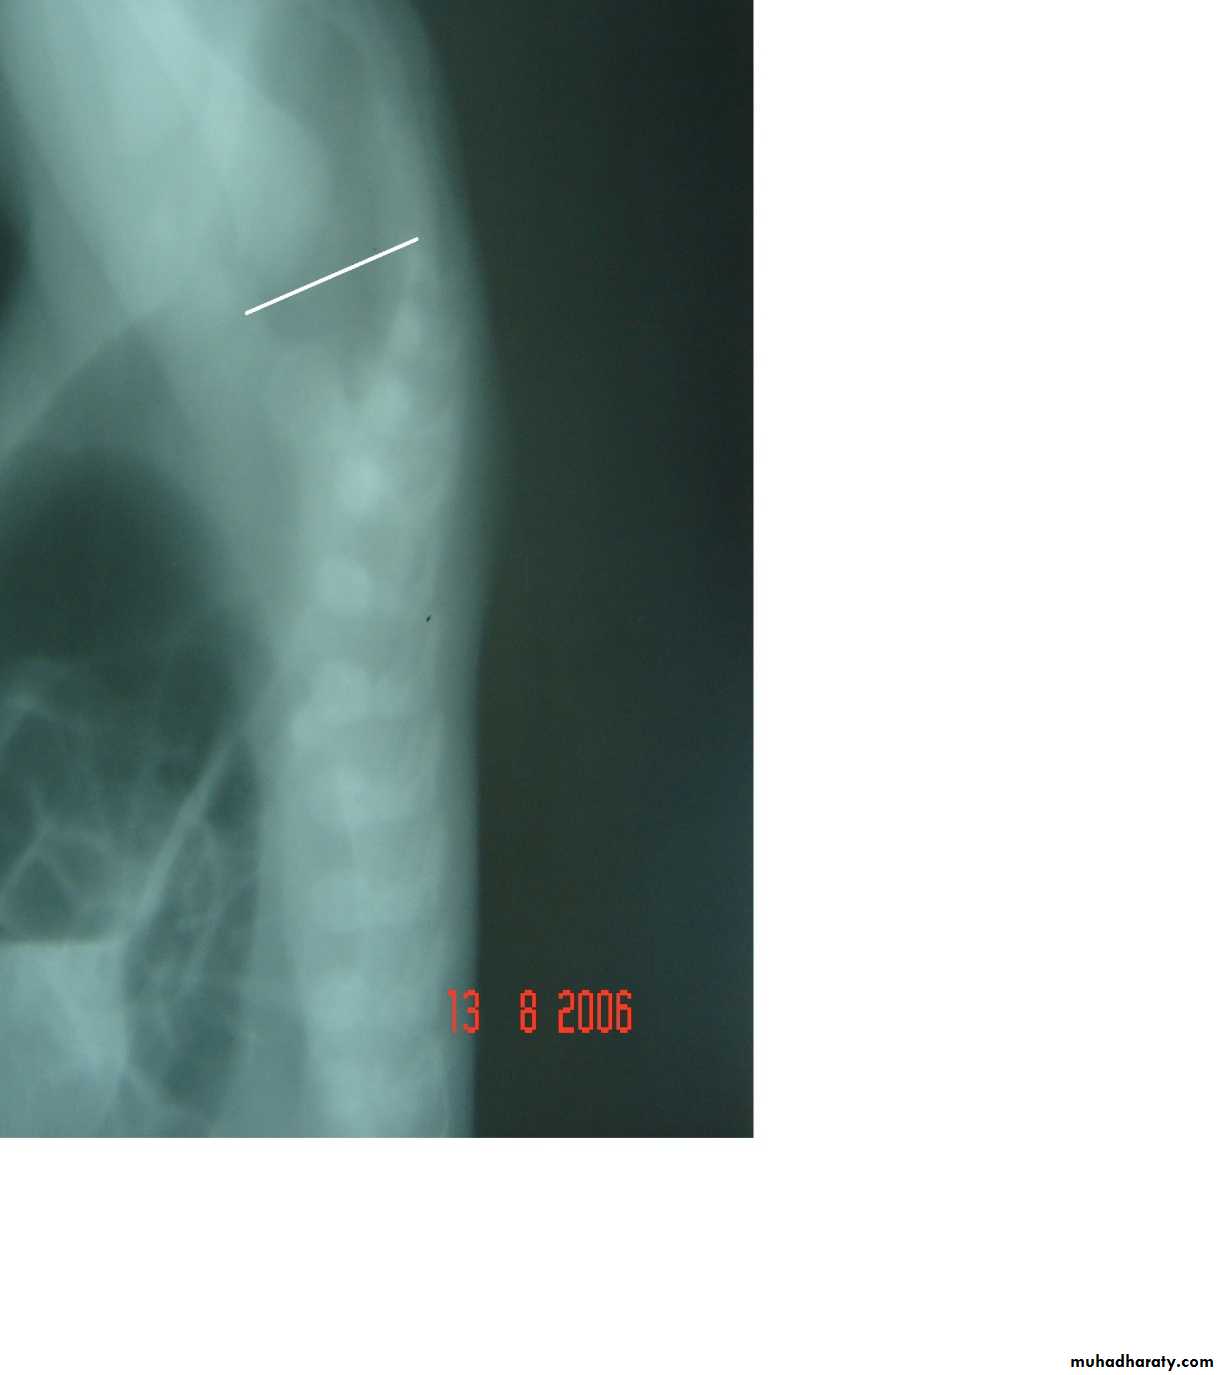

Diaphragmatic eventration

plication